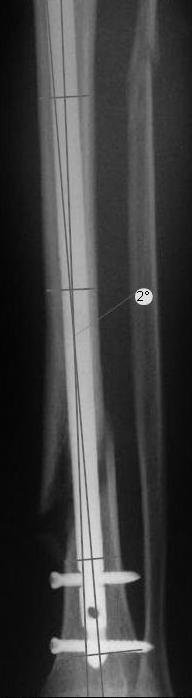

Вы бы стали оперировать или рекомендовали бы своему родственнику оперироваться из-за 2 градусов?

Динамизировать, выкрутив проксимально все винты, на сроке 8 недель ихмо достаточно.

КА> Вот именно количественный, т.е. сколько градусов в вальгусе

КА> допустимо и при каком диастазе в мм или в % от толщины диафиза.

Антон, дорогой, важнее вальгуса тут близость верхнего отверстия к перелому и отсутствие уверенности в быстром сращении из-за большого

диастаза.

В Кемпбелле можно прочитать, что Fractures in the distal third of the tibia had the highest frequency of nail breakage.

Вообще, этот вопрос обсуждался давно, и еще в статье R. Bucholz (1987) про переломы гвоздей указывалось, что расстояние от ближайшего отверстия до перелома должно быть не менее 5 см, иначе есть угроза усталостного перелома. По литературе переломы гвоздей в нижней трети

tibia достигают 4,3%.